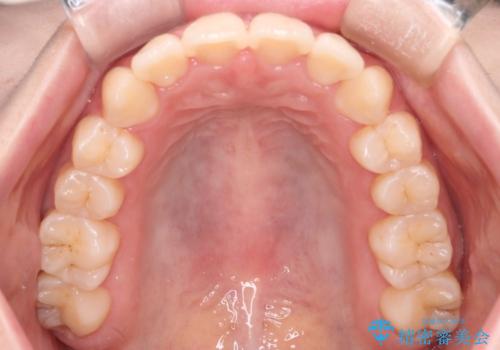

【インビザライン】マウスピースで開咬改善

歯の移動量が多いケースでしたが、患者様にマウスピースの使用とゴム掛けを頑張っていただいたので

リファイメント1回のみで治療を終わることができました。